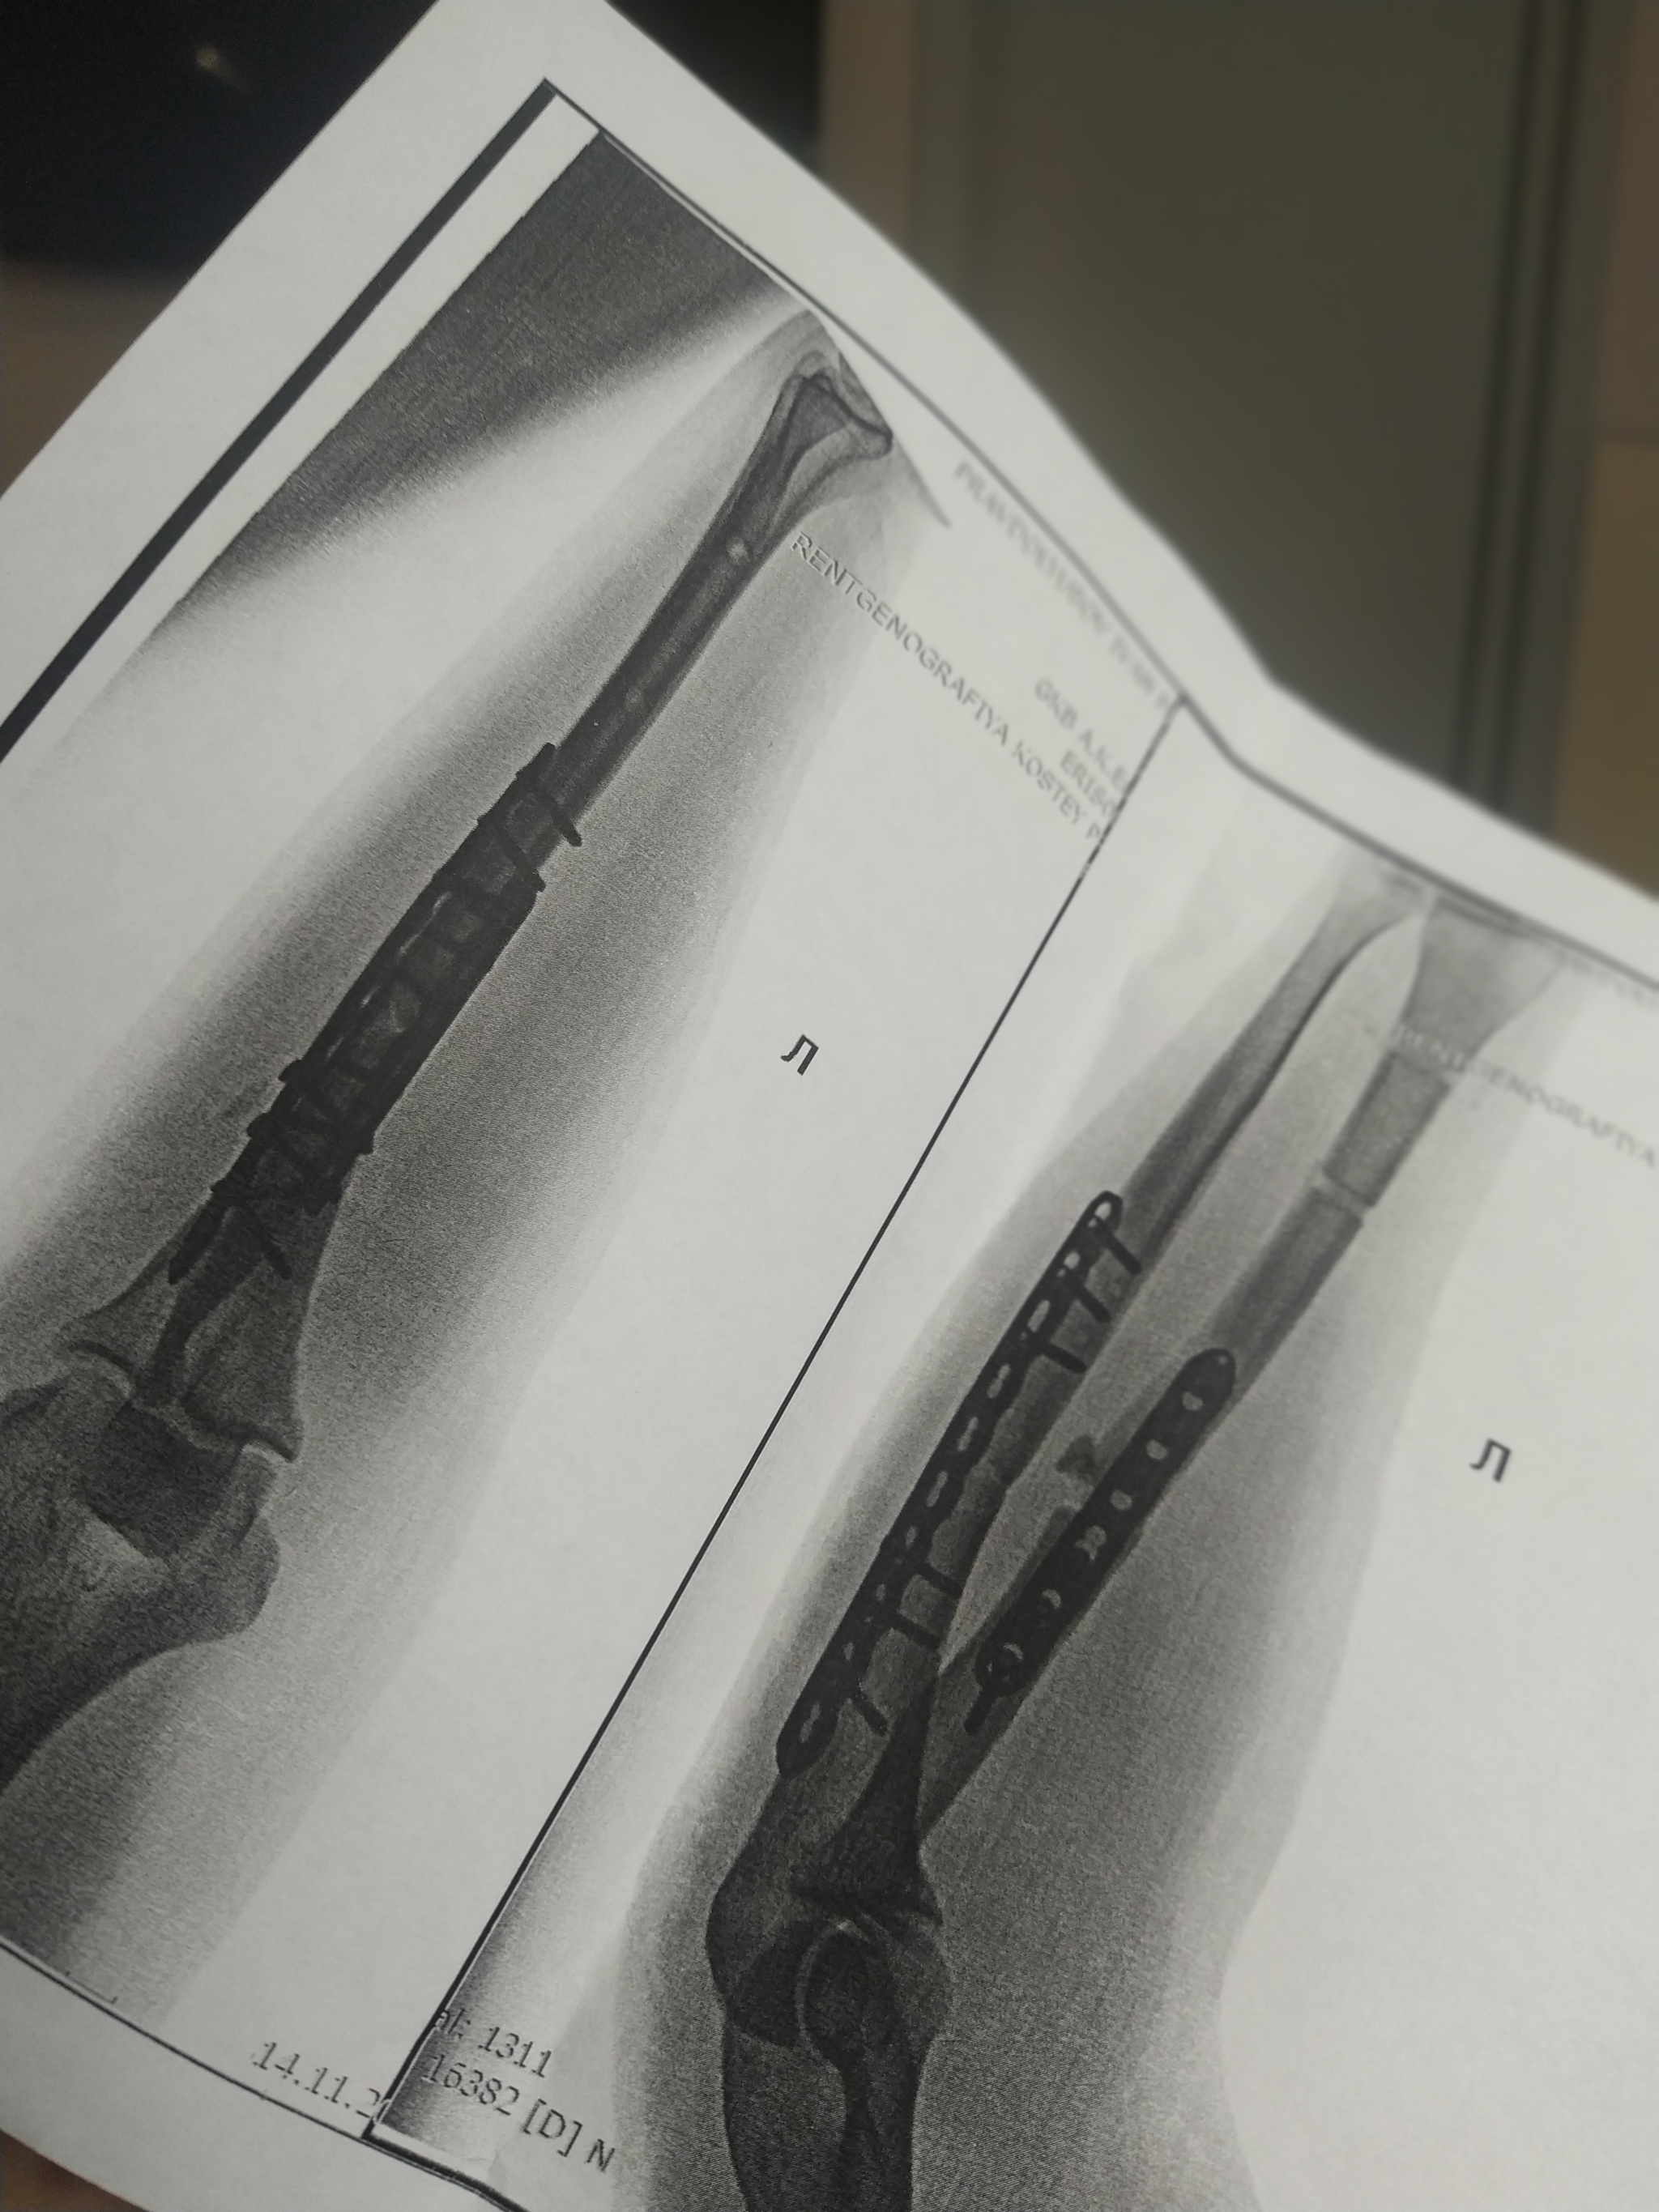

Интересно, у меня тоже левая нога, 2 пластины на МБК и ББК, ходил недели 3 на iwalk, потом на двух подмышечных костылях, потом на одном, сейчас трость, пытаюсь ходить без неё, тоже могу начать прогулку без трости, потом в конце приходится помогать.

У меня ДТП. Я за рулём, на меня на встречку вылетел лоб в лоб. Очнулся в больнице. Левую ногу и левую руку собирали. Вот на руке шрам страшный. Из последствий нога короче на 3см. Спец обувь. А так, спустя 1,5 года всё отлично)))) но металл пока во мне. Не знаю, буду вынимать или нет. И так натерпелся операций, не хочу....